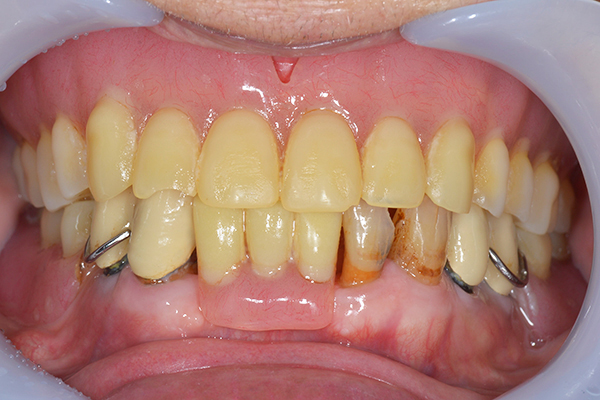

前歯が折れて当院にいらっしゃいました。 過去に下の入れ歯を作ったが、合わなくなってずっと入れ歯をいれていらっしゃらない患者様でした。 これは奥歯で噛むことができないため、前歯で噛むことを繰り返したために、負担に耐えられなくなった前歯が折れてかぶせ物ごと 外れてしまったのだと考えられます。 痛くない、違和感の少ない、下の入れ歯を作ることがこの方のゴールであると考えられました。

金属を使用して、薄く違和感が少ない入れ歯が完成しました。 また、見た目にも気を使い、バネが見えにくい様な構造にしました。

入れ歯をお口の中にいれた状態です。前歯もMTMといって、歯を少し引っ張り出す処置を行なったことで、しっかり残せて、またかぶせ物をしました。

義歯は下顎で、しっかり噛めること、違和感の少ないものという希望があったため、なるべく入れ歯を薄く作成するために金属をしようした義歯とした。

また、見た目もあまり義歯が目立たない様に、バネの部分を見えにくいように作成した。